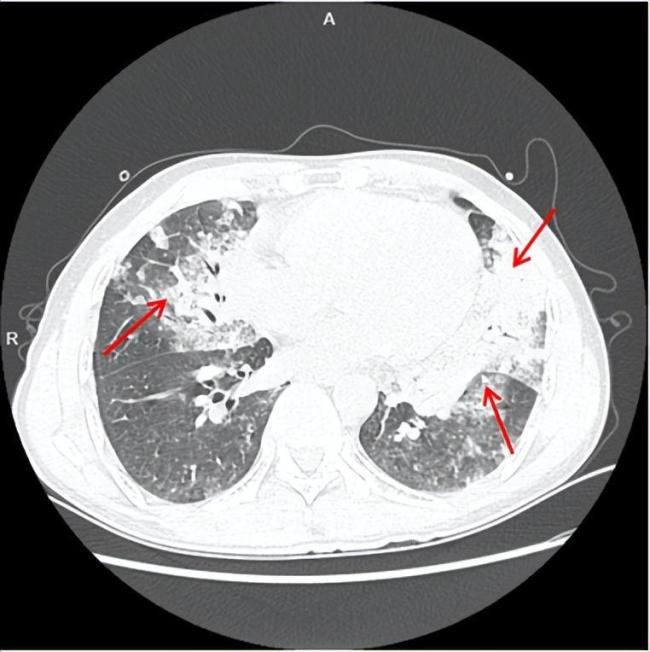

入院时,肺部CT影像显示左肺舌叶和右肺中叶渗出实变,左肺下叶散在磨玻璃影。由于病情危急,阿勇被紧急转诊到温州医科大学附属第一医院急诊科。进一步检查发现两肺多发渗出灶伴局部实变,出现大面积白肺,医生诊断为急性外源性脂质性肺炎。

医护人员迅速将阿勇送入重症监护室(EICU),进行了气管插管接呼吸机辅助通气和肺泡灌洗术,灌洗出大量黄褐色液体,并给予大剂量激素对抗脂质性炎症和抗感染治疗。第二天,阿勇的胸痛发热症状明显好转,经过一周的治疗、护理及多次肺部支气管镜检查和肺泡灌洗,他虽然脱离了生命危险,但仍需进行肺功能康复。